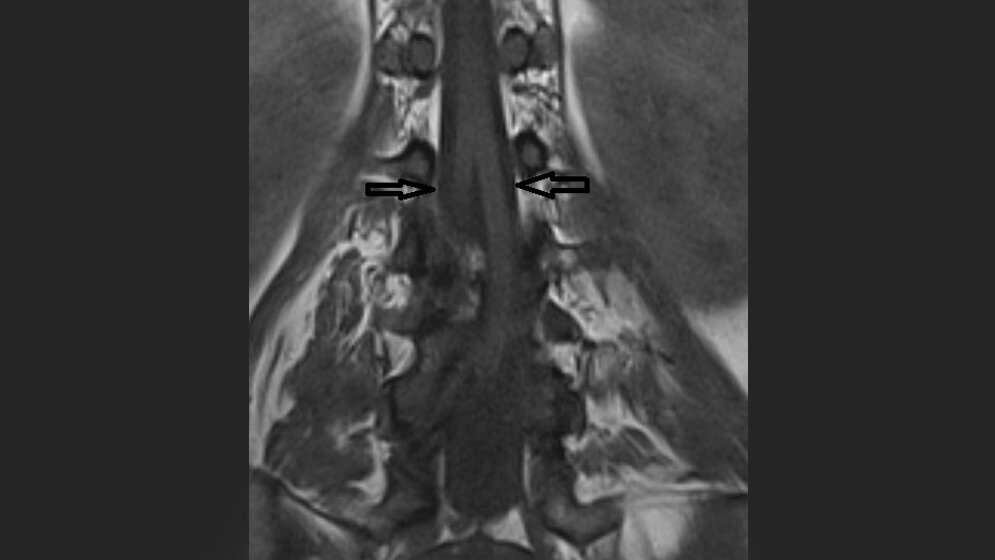

Die Diastematomyelie ist eine komplette oder partielle Teilung des Rückenmarks in 2 Teile, jeweils mit eigenem Zentralkanal und umgebender Pia. Patienten mit 2 Duraschläuchen gehören zum Typ 1 der Diastematomyelie, die mit nur einem angelegten Duralschlauch zum Typ 2. Die Anomalie kann auch erst im fortgeschrittenen Alter entdeckt werden.

Diastematomyelia is complete or partial sagittal splitting of the spinal cord into 2 hemicords, each with its own central canal and pia surrounding it. Patients with double dural tubes have type 1 and patients with single dural tube have type 2 of diastematomyelia. At advanced age diastematomyelia can be first discovered.